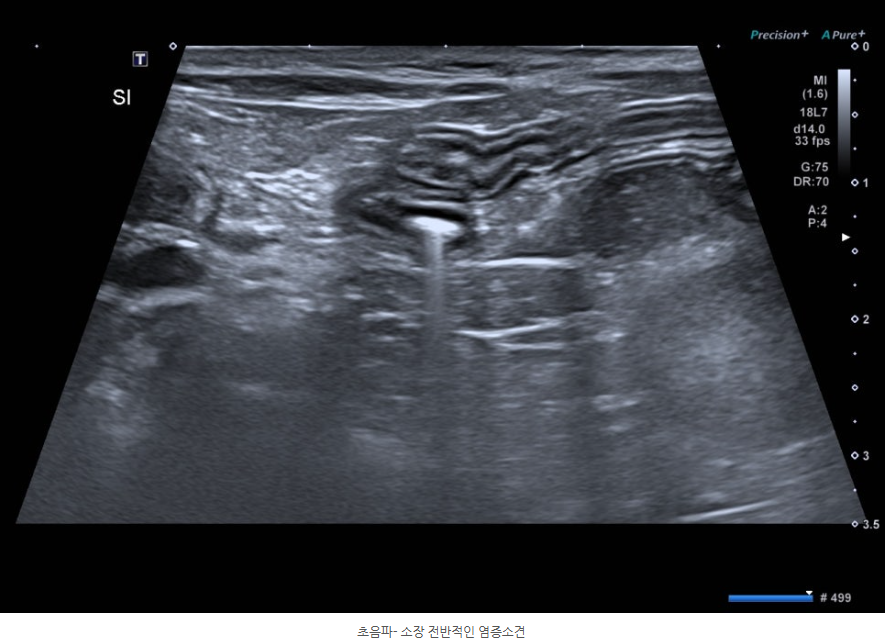

복부 초음파 검사 상에서는 대장 내 다량의 수양성 변과 소장의 전반적인 염증 소견이 확인되었습니다.

장 상태를 재검하기 위한 복부 초음파에서도 이전에 보이던 대장 내 변의 경도가 증가하고 소장의 염증 소견이 해소된 것을 확인할 수 있었습니다.